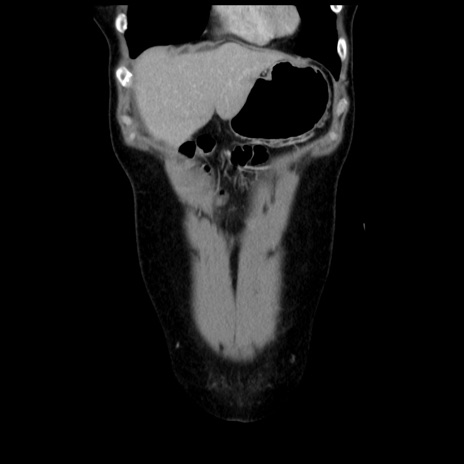

横断像